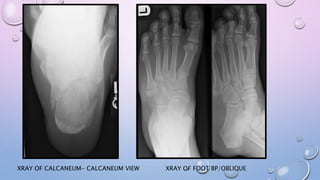

XRAY OF FOOT BP/OBLIQUEXRAY OF CALCANEUM- CALCANEUM VIEW

FRACTURE AROUND ANKLEOR FOOT- XRAY OF ANKLE AP/ LAT/ MORTISE VIEW

XRAY OF FOOTBP/OBLIQUEXRAY OF CALCANEUM- CALCANEUM VIEW